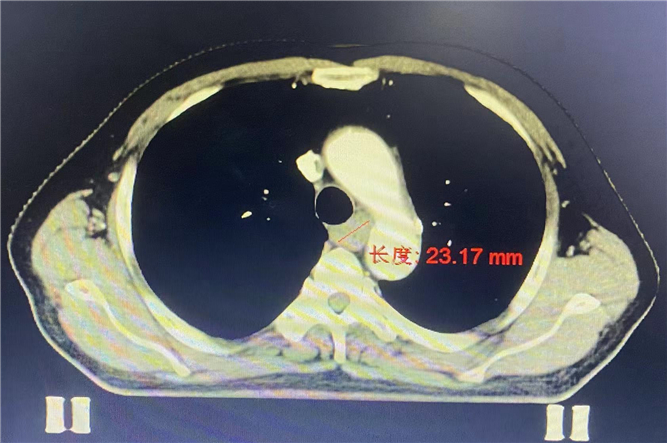

住院后,張大爺進行了胸腹盆CT,顯示:食管胸上段管壁增厚,符合惡性征象;右側(cè)鎖區(qū)及縱隔多發(fā)淋巴結(jié)轉(zhuǎn)移,進一步診斷為:食管鱗癌(cT2-3N1M1a IV期)。

治療前:23.17mm